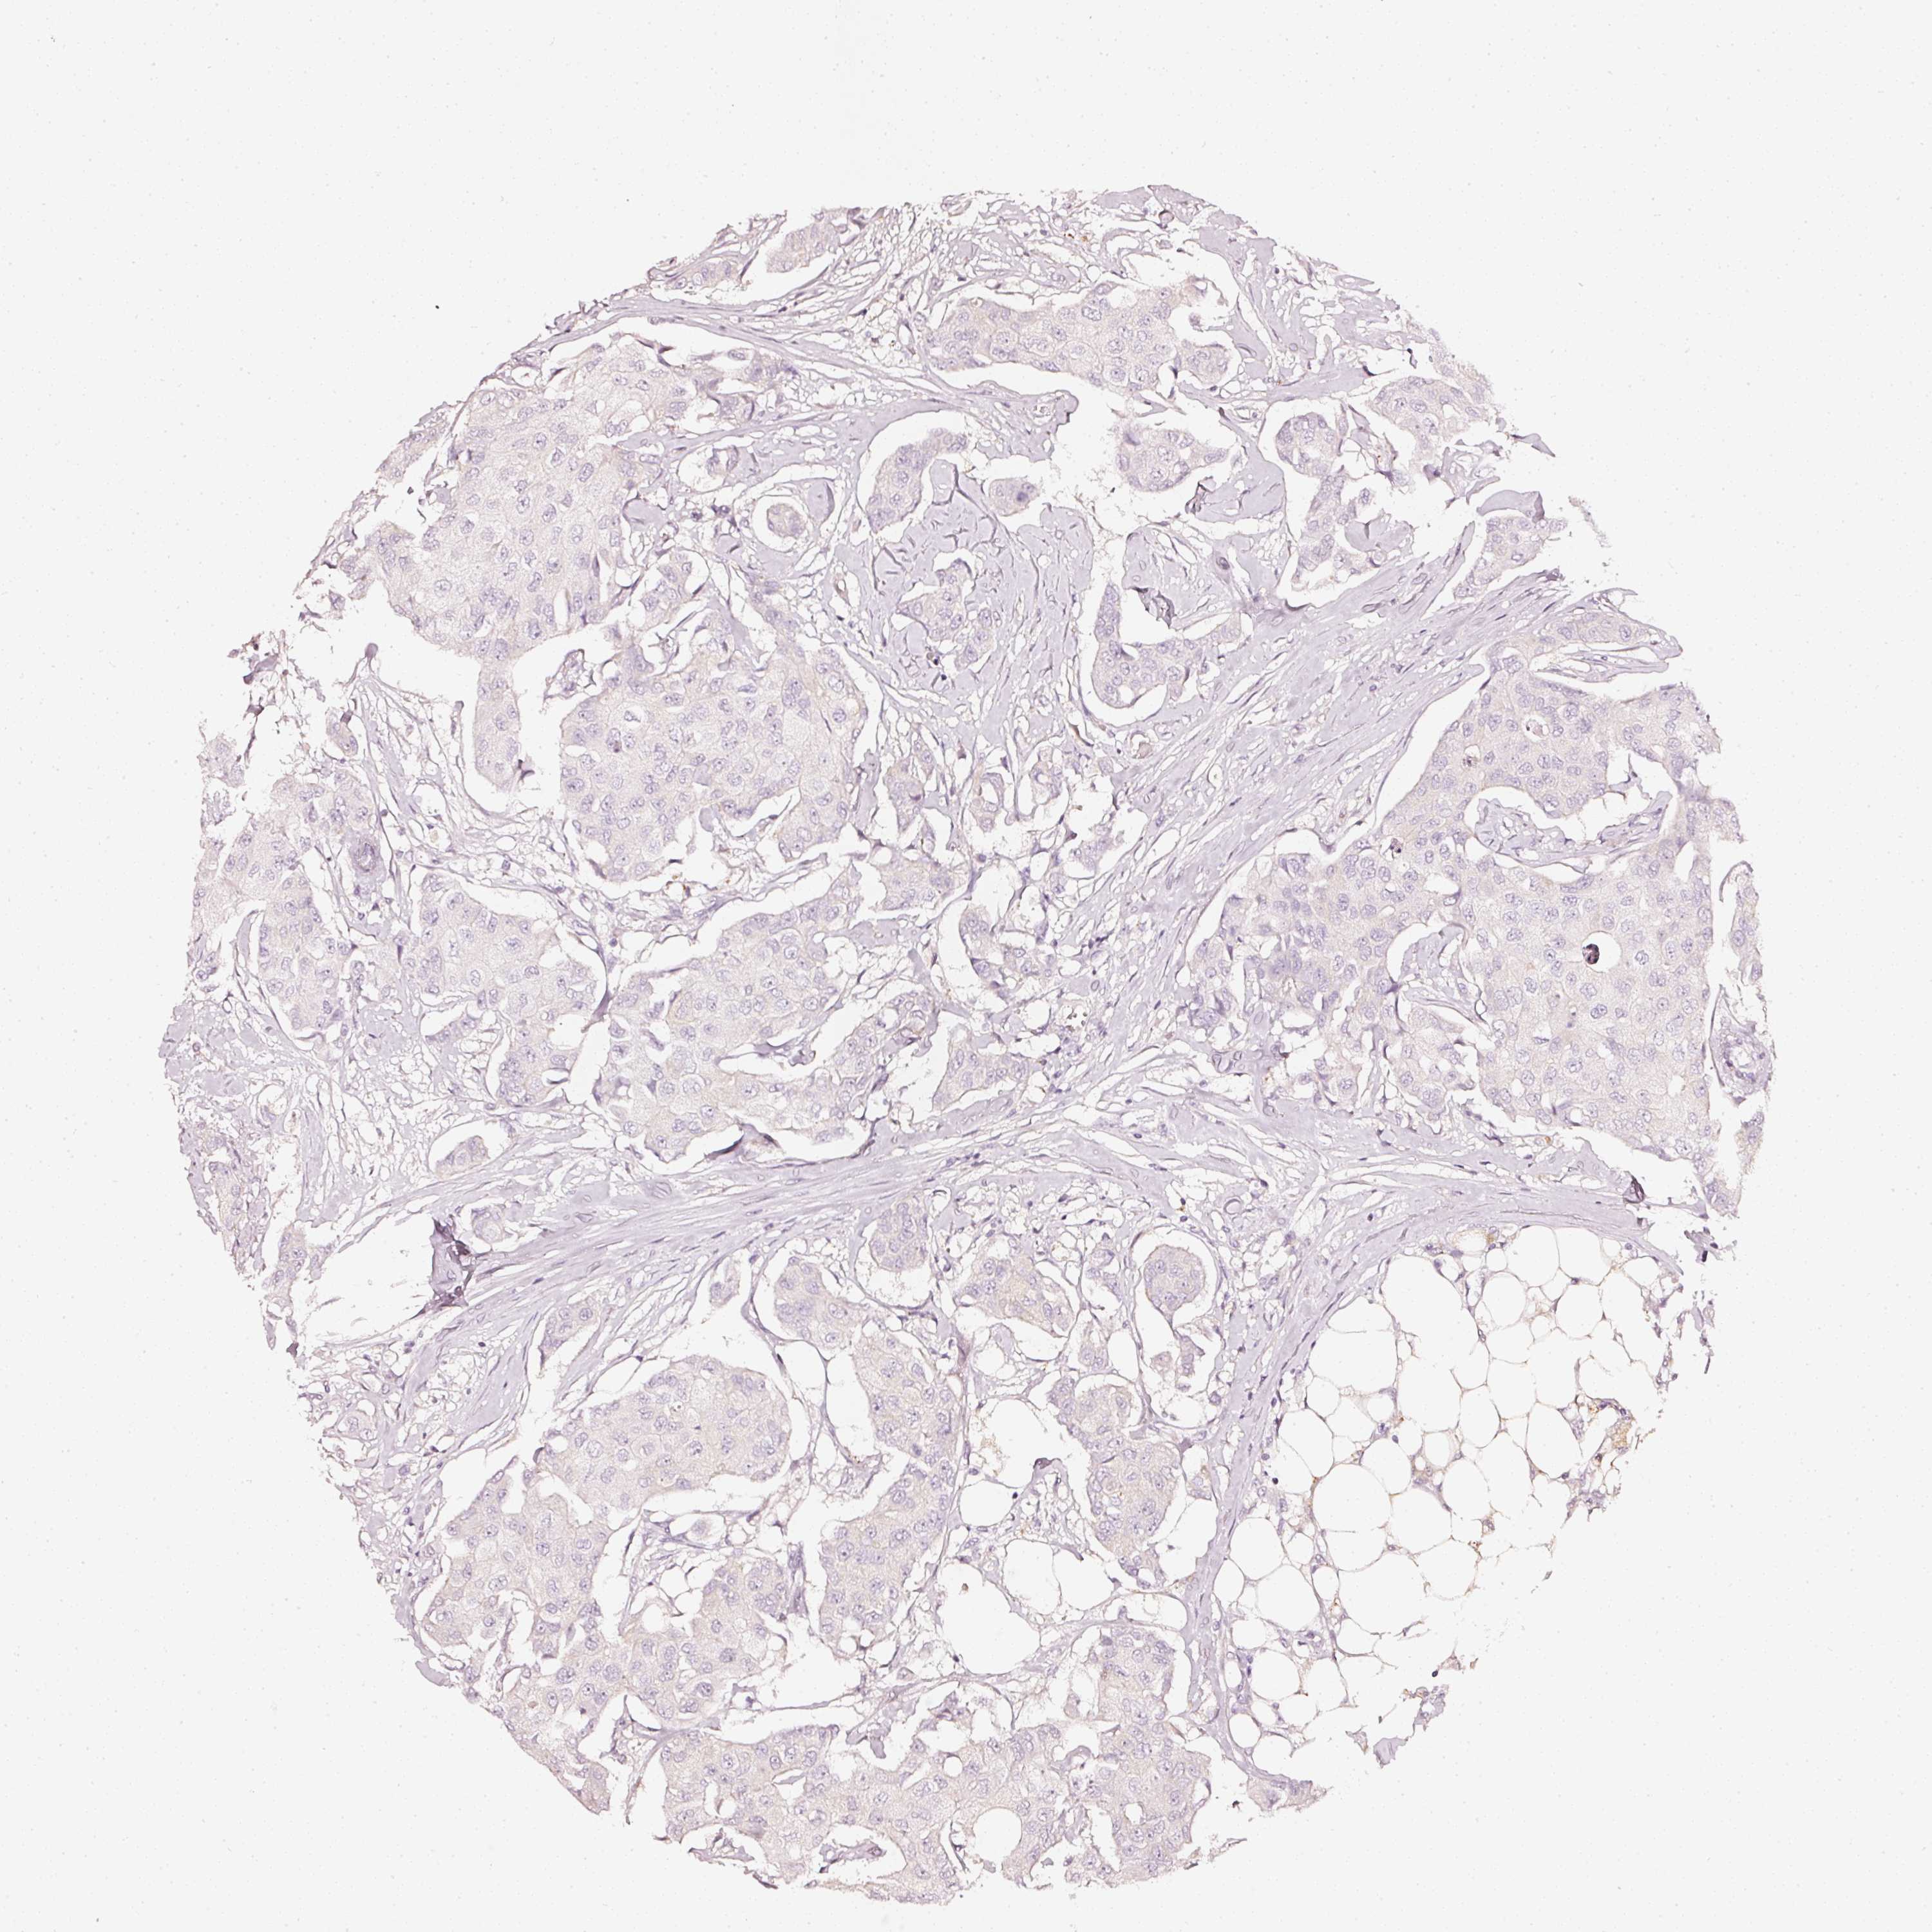

CANCER BREAST CANCER Show tissue menu

Breast cancer

Human cancer